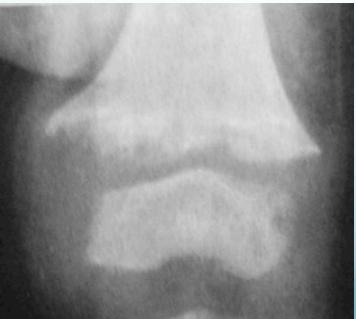

- Widened physis (epiphyseal growth plate)

- Cupping of metaphyseal end (weak new bone)

- Irregular metaphyseal end

- Osteopenia (decreased bone density)

- Thin cortex

- Widened physis (first and most prominent finding)

- Metaphyseal changes:

- Cupping (due to weak new bone)

- Irregular margins